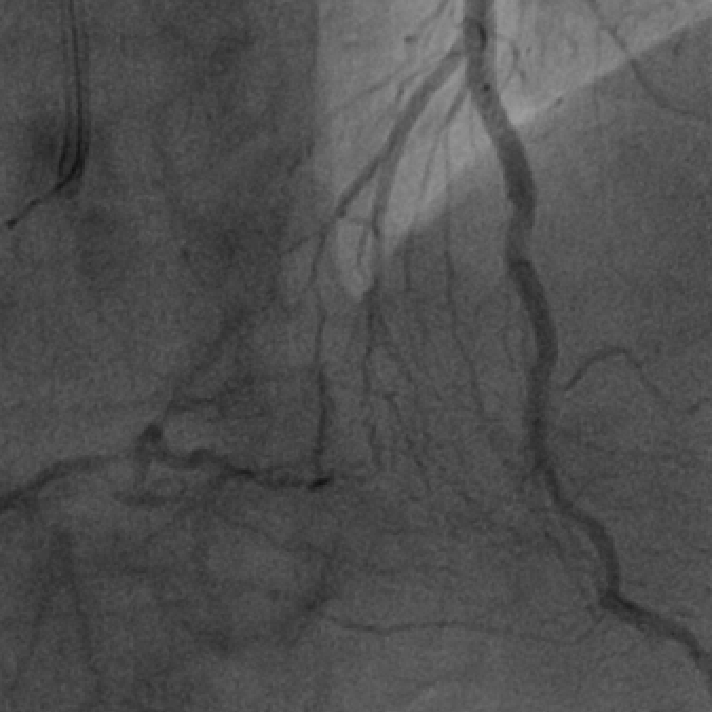

左冠造影

右冠造影